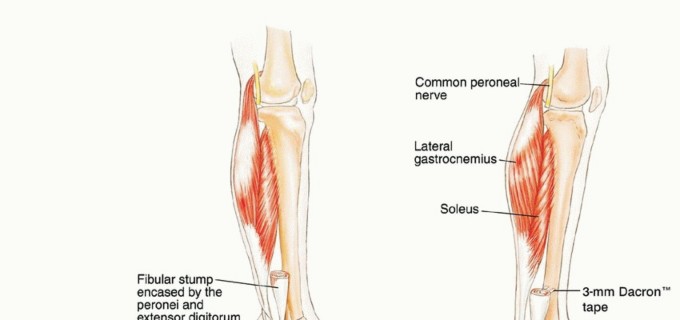

تشريح الشظية القريبة

تُعد الشظية القريبة (الرأس والجزء العلوي من العظم) موقعًا رئيسيًا لالتصاق الرباط الجانبي الوحشي (LCL) ووتر العضلة ذات الرأسين الفخذية. هذه الروابط ضرورية لاستقرار مفصل الركبة الجانبي. الأهم من ذلك، أن العصب الشظوي المشترك يلتف حول قاعدة رأس الشظية ليدخل نفق العضلة الشظوية الطويلة، مما يجعله عرضة للإصابة أثناء جراحة الأورام في هذه المنطقة.

أنواع الاستئصال الجراحي للشظية القريبة

هناك ثلاثة أنواع رئيسية من استئصال الأورام حول الشظية القريبة:

-

الكشط (Curettage):

- الإشارة: يُستخدم للأورام الحميدة العدوانية والأورام الغرنية منخفضة الدرجة المرتبطة بتدمير قشري بسيط وامتداد خارج العظم ضئيل.

- الإجراء: يتم إزالة الورم يدويًا بواسطة مكشطة، ثم تُستخدم مثقاب عالي السرعة لتنظيف جدران تجويف الورم بدقة لضمان إزالة أي مرض مجهري متبقي.

- الحفاظ: يتم الحفاظ على العصب الشظوي المشترك والأوعية الدموية.

-

الاستئصال من النوع الأول (Type I Resection):

- الإشارة: يُستخدم لعلاج الأورام الحميدة العدوانية والأورام الغرنية منخفضة الدرجة التي تسببت في تدمير قشري كبير للشظية القريبة.

- الإجراء: يشمل إزالة الشظية القريبة، وغلاف عضلي رقيق من جميع الأبعاد، وموقع ارتباط الرباط الجانبي الوحشي (LCL). يتم الحفاظ على العصب الشظوي المشترك وفروعه الحركية، ويتم استئصال المفصل الظنبوبي الشظوي داخل المفصل.

- الحفاظ: يتم الحفاظ على العصب الشظوي والشريان الظنبوبي الأمامي عادةً.

-

الاستئصال من النوع الثاني (Type II Resection):

- الإشارة: يُستخدم لعلاج الأورام الغرنية عالية الدرجة، والتي عادةً ما يكون لديها تدمير قشري كبير مع امتداد خارج العظم.

- الإجراء: يشمل إزالة الشظية القريبة والمفصل الظنبوبي الشظوي، والحجرات العضلية الأمامية والجانبية، والعصب الشظوي، والشريان الظنبوبي الأمامي بشكل كامل. يتطلب هذا النوع ربط الشريان الظنبوبي الأمامي وقد يتطلب أيضًا التضحية بالشريان الشظوي.

- الحفاظ: لا يتم الحفاظ على العصب الشظوي والشريان الظنبوبي الأمامي.

يوضح الجدول التالي الهياكل التشريحية التي يتم إزالتها مع أنواع الاستئصال المختلفة للشظية القريبة: